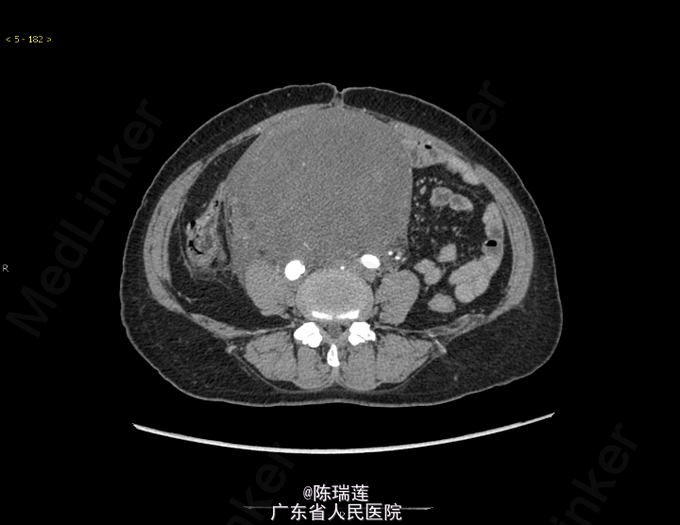

发现下腹部肿块2月。 患者入院前发现下腹部肿块,伴下腹酸胀,无腹痛、腹泻,无尿频、尿急、尿痛,无里急后重等不适,于当地医院就诊,B超示:盆腔实性肿块(149*117mm),性质待定;子宫缩小,符合绝经期子宫改变;盆腔CT示:腹腔-盆腔占位,(14.3*12.3*14.9cm),未予特殊处理。

查体:右侧附件区可触及20cm类圆形包块,质地较硬,无压痛,活动欠佳。左侧附件区未触及 ,其余无特殊。 辅查:全腹部增强CT示:右侧附件区见一巨大肿块,上缘达L3椎体水平,最大层面大小约118mm(L)×137mm(W)×148mm(H),推压周围膀胱及肠管,平扫密度较均匀,呈稍低密度。 术后肿物病理为(腹膜后肿物)脂肪肉瘤。

诊断:(腹膜后肿物)脂肪肉瘤 处理:行腹膜后肿物切除+肠粘连松解+膀胱右侧输尿管植入。术中见大小30*25*18cm肿物,与肠管紧密粘连,探查子宫及双侧附件外观未见异常,肿物来源于后腹膜,与肠管关系密切,双侧输尿管走形分辨不清。